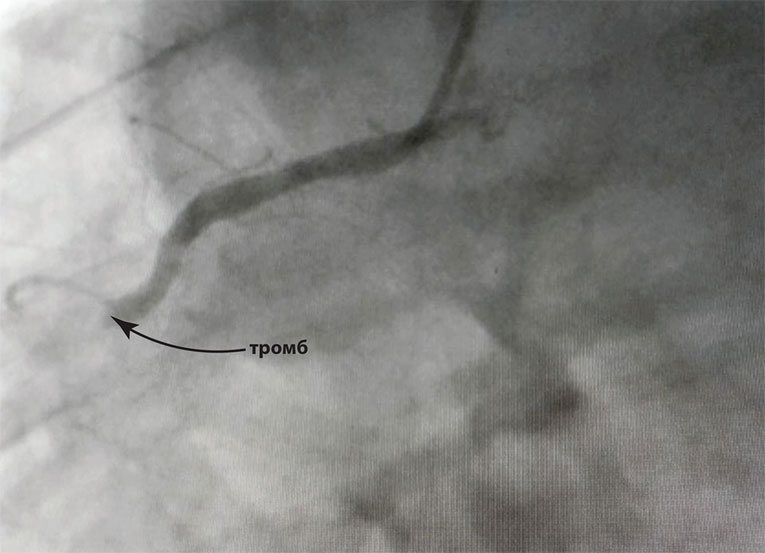

Тромб в правой коронарной артерии

Иллюстрация к книге — Как жить после инфаркта [i_017.jpg]

Пациенты и их родственники часто не понимают разницу между двумя этими абсолютно разными медицинскими вмешательствами – СТЕНТированием и ШУНТированием коронарных артерий. Разница всего лишь в нескольких буквах, но это две принципиально отличные друг от друга операции, и выполняют их соответствующие специалисты. СТЕНТирование – удаление тромба в коронарной артерии и установка стентов – малоинвазивная операция, которая проводится через небольшой прокол в коже на запястье или в паху. Пациент находится при этом в сознании, процедура длится не более часа.